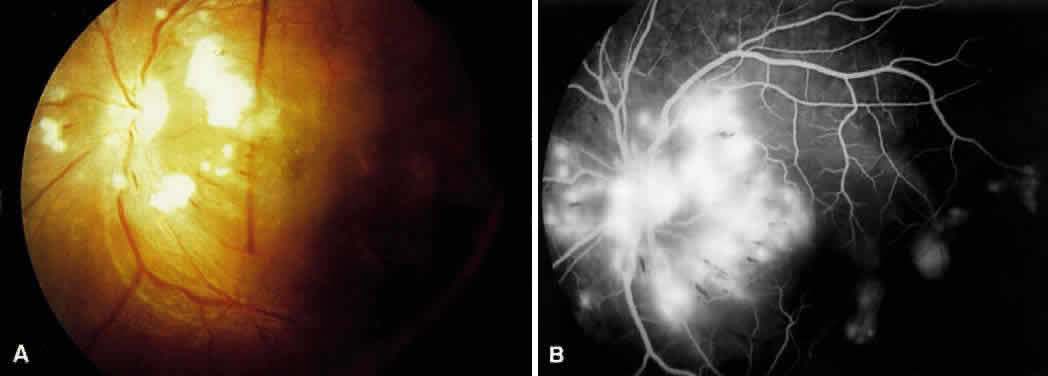

HYPERTENSIVE NEUROPATHY

In malignant hypertension, one of the earliest changes seen is optic nerve head edema6,32:

Clinical Findings in Neuropathy

• Optic disc edema

• Optic disc pallor

• Optic disc ischemia

The clinical appearance is indistinguishable from other causes of optic nerve head swelling, such as elevated intracranial pressure (Fig. 10). The mechanism of disc swelling remains controversial. In Tso and Jampol's study of baboons,8 the edema was believed to be the result of an accumulation of axoplasmic components. However, they could not determine whether this accumulation was related to ischemia or to some mechanical phenomena. Kishi and associates6 demonstrated axonal hydropic swelling that was secondary to ischemia. They later concluded that the ischemia produced was related to vasoconstriction of the peripapillary choroidal and optic nerve head vessels.11,32 The direct vasoconstrictive and occlusive properties seen in hypertensive choroidopathy lead to ischemic changes in the optic nerve head because it receives most of its blood supply from the peripapillary choroidal vessels.11,32,33 Further, vascular endothelial substances can diffuse easily into the optic nerve head from the surrounding choroidal bed and cause vasoconstriction of the optic nerve head vessels.11,32,33

Fig. 10. A. Disc photos showing optic nerve head edema with cotton-wool spots and splinter hemorrhages seen in hypertensive optic neuropathy. B. Fluorescein angiogram shows hyperfluorescence caused by late leakage.

Late findings seen in hypertensive neuropathy are optic nerve head pallor and atrophy resulting from chronic ischemia. The clinician must be careful to rule out other possible causes of these findings, including anterior ischemic optic neuropathy and temporal arteritis when evaluating patients for hypertensive optic neuropathy.